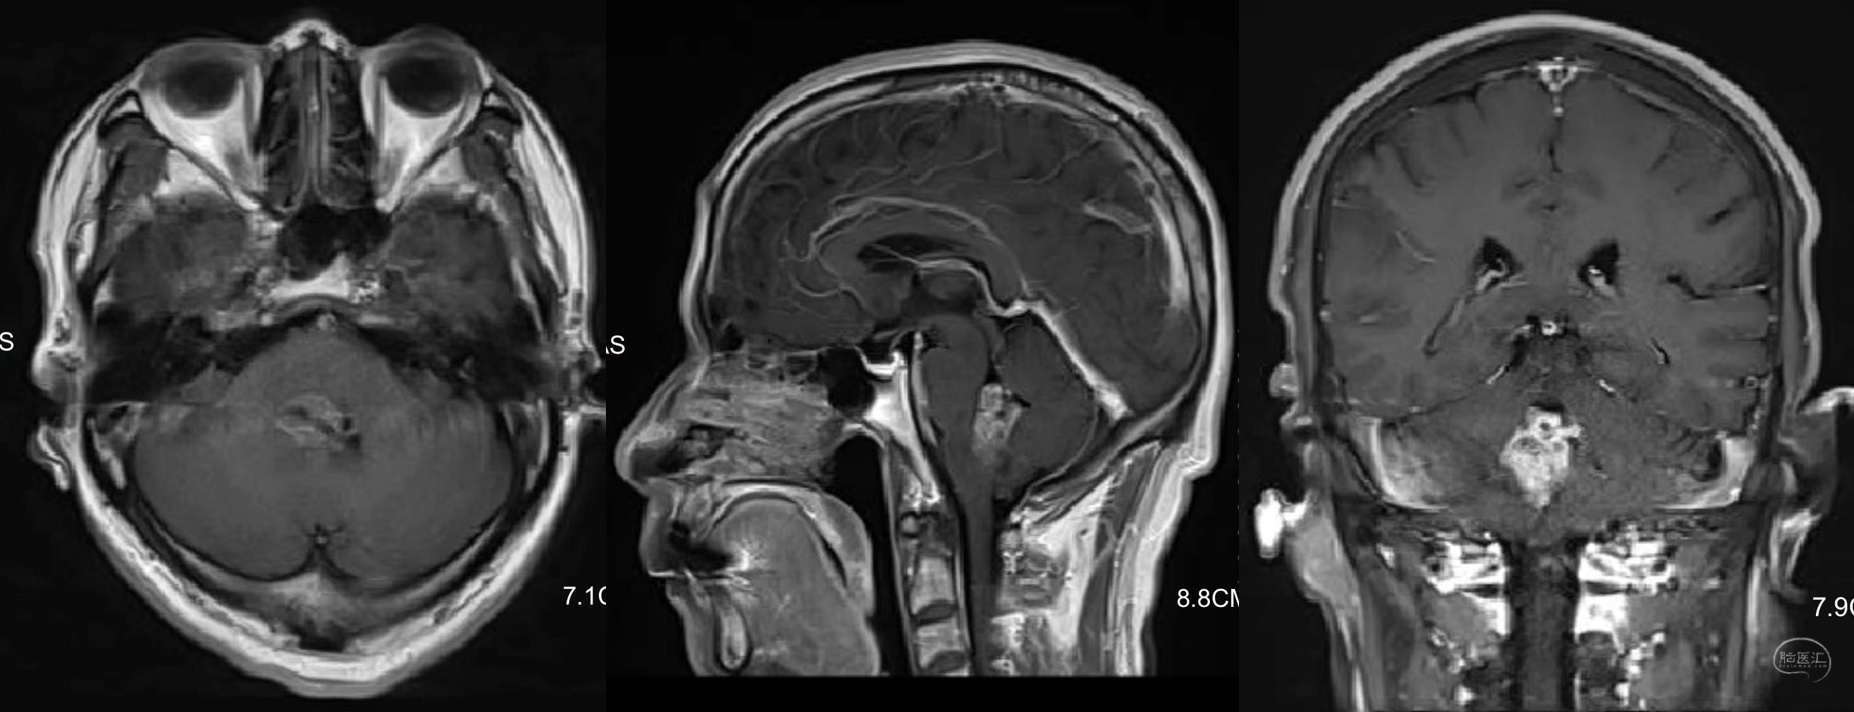

术前磁共振提示四脑室肿瘤,室管膜瘤考虑。